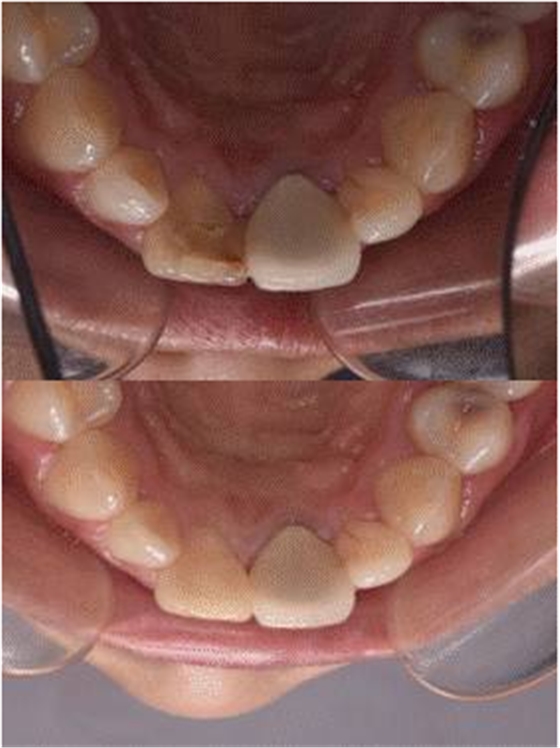

口腔檢查:口腔衛(wèi)生狀況一般,11牙冠變色,近中鄰面見齒色填充物,舌側窩內(nèi)見白色充填物,邊緣見黑色齲壞物,近中探及懸突,叩痛(土),松(—),冷診無反應;21烤瓷全冠修復,烤瓷冠顏色未知,唇側齦緣發(fā)黑,叩痛(土),松(—)。圖1/2

圖1 治療前患牙唇側觀

圖2 治療前患牙舌側觀

圖11 治療后唇側觀

圖12 治療后舌側觀

圖13 治療前后唇面對比

圖14 治療前后舌側對比